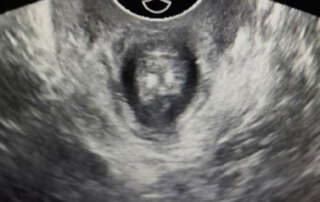

Funneling of the urethra in Valsalva (Article 1) and a phrenic (Diaphragm) endometriosis